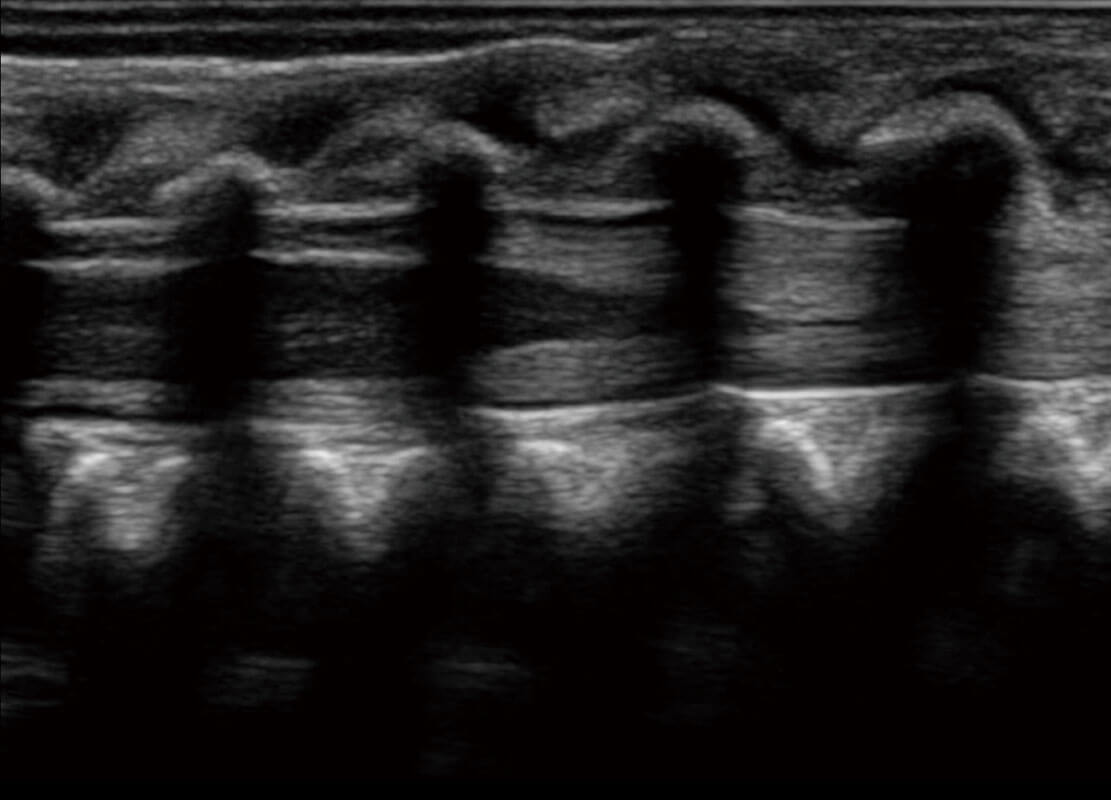

新生儿脊髓圆锥